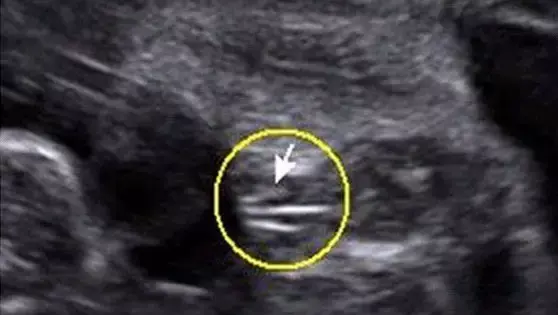

還會告訴你,這下面的三條白線是明顯的女寶特征,如果沒有看到明顯的三條白線,就看兩腿之間有沒有突出的東東,且中間有小凹槽的,就是女寶寶。???(真的假的?)

而這些,都可以肯定地告訴大家——沒有科學依據!

準媽媽們的孕囊看上去形狀有所區別與胎兒性別沒有關系。一般發育較好的孕囊是圓扁形的,但是有時孕囊會隨宮腔的形狀而變長。孕囊的形狀由其張力和含羊水量決定的,會自行改變形狀。